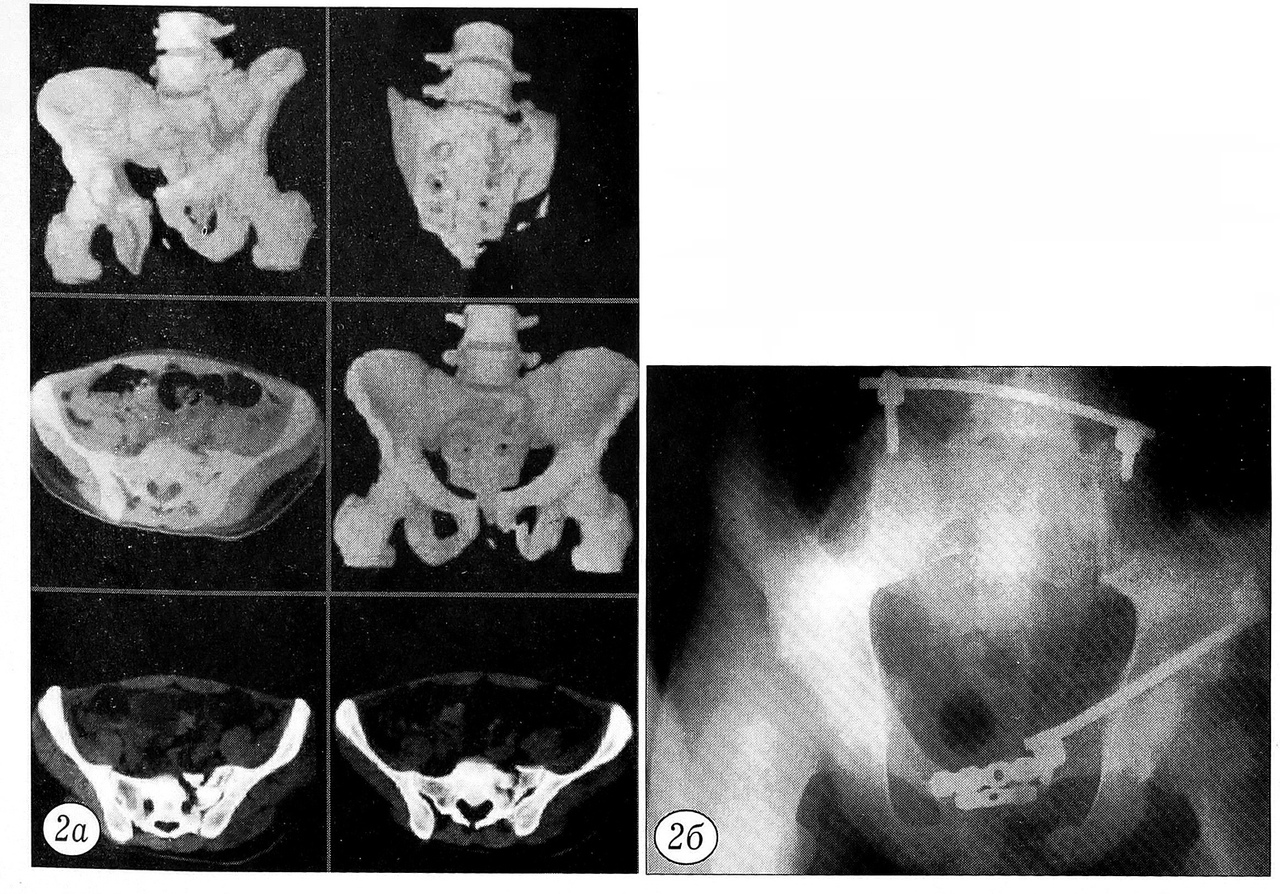

Если переломы ветвей лонных костей сопровождались разрывом лонного симфиза, для его фиксации применяли накостные опоры системы в виде одной или двух реконструктивных пластин с 3~5 отверстиями (рис. 2).

Рис. 2. Пострадавший 27 лет с абсолютно нестабильным повреждением таза: закрытым переломом ветвей левой лонной кости и левой боковой массы крестца. Произведена фиксация тазового кольца с использованием накостных опор. а — компьютерная томограмма таза при поступлении больного в клинику; б — рентгенограмма таза после оперативного лечения.